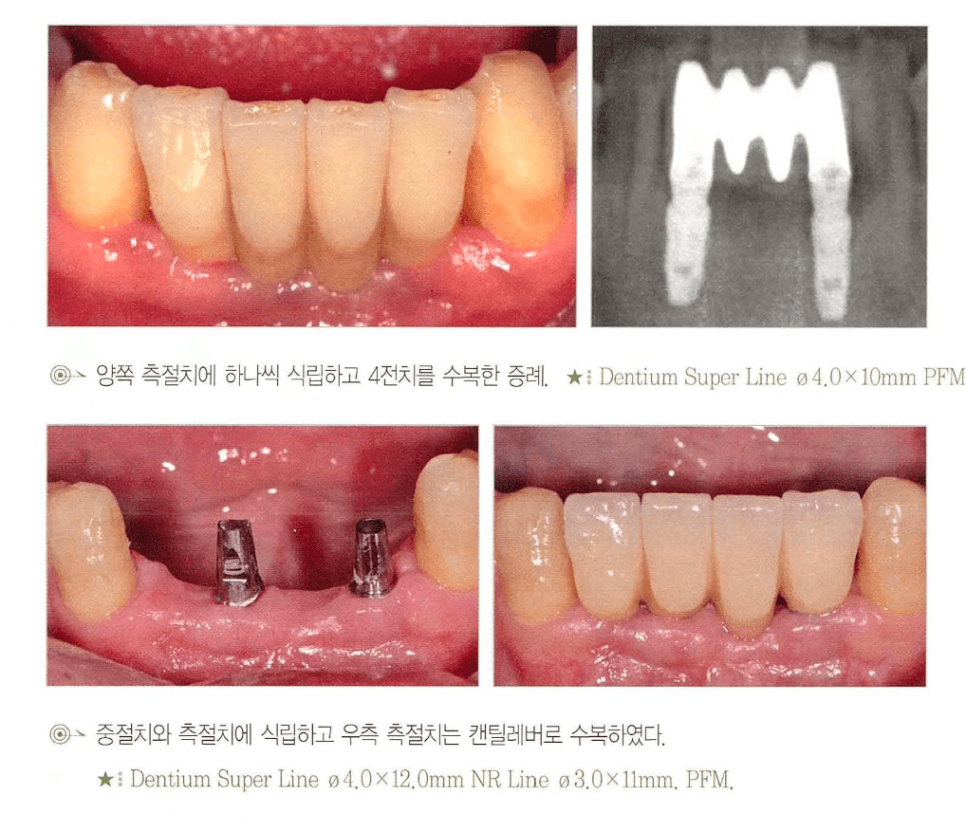

[그림 5] 하악 전치부 수복의 두 가지 설계. 위: 양측 측절치에 각 1개씩 임플란트를 식립해 4전치를 수복 / 아래: 중절치+측절치에 임플란트를 식립하고 양쪽 끝을 캔틸레버로 수복.

- 상악 4전치 — 임플란트 2개(보통 양측 측절치 위치)로 충분한 경우가 많습니다. 중절치와 측절치 한쪽 조합 + 반대측 캔틸레버 설계도 흔히 사용됩니다.

- 하악 4전치 — 하악 전치부는 구강 내에서 골질이 가장 단단한 영역이므로 여유가 있습니다. 임플란트 2~3개로 pontic을 포함한 4-unit 수복이 일반적입니다.